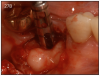

As mentioned earlier, dental implants require daily brushing and flossing, just like teeth. If plaque is allowed to build up around the implant, then peri-implant mucositis (gingivitis) or peri-implantitis may occur. (Figure 26) Signs of this condition include redness, bleeding when brushing and pocket depth increase in the area.

Figure 26 – Peri-implantitis – note the exposed implants, receding gingiva and plaque present on the exposed implant surfaces

Figure 26